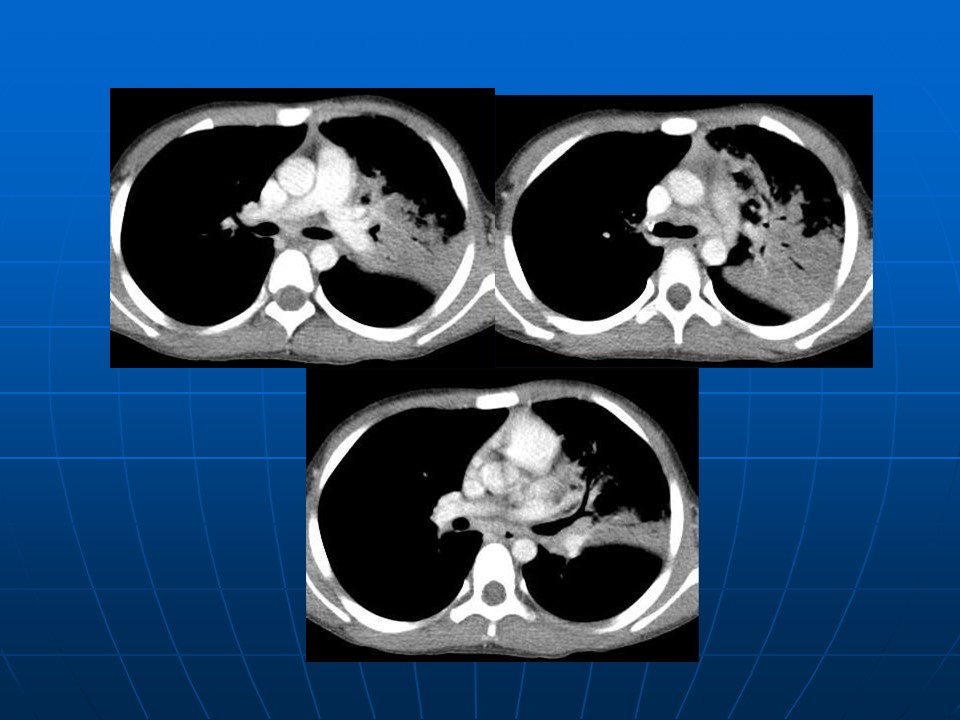

【病例】矽肺1例CT影像表现